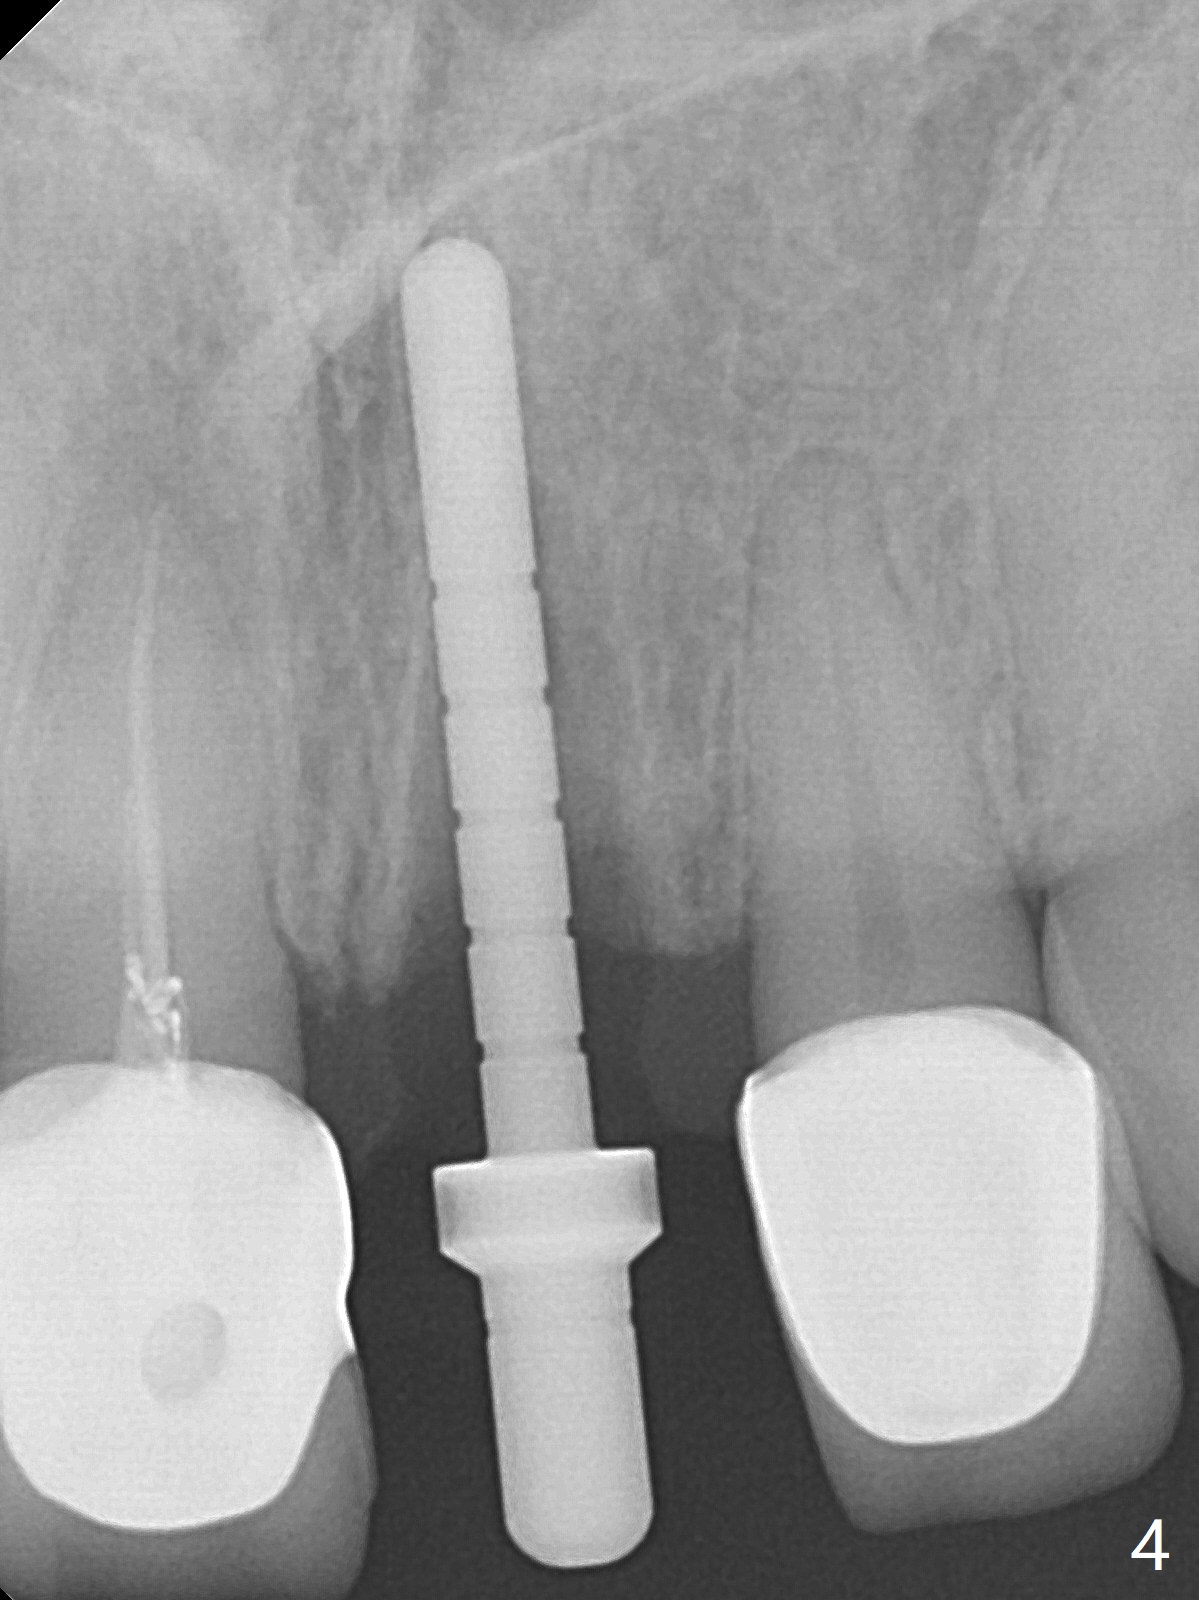

After sectioning the splinted crowns at #8 and 9 (Fig.1,2 (*: open bite)), the tooth #9 is deemed nonsalvageable because of caries and the crown/retainer of #8 is recemented. The trajectory of initial osteotomy is off (Fig.3 (red line: ideal trajectory)). Using Lindamann bur twice does not improve the trajectory (Fig.4,5). It appears that a new osteotomy should be established in the distal wall of the socket (Fig.5 red line (initial entry point and angle), Fig.6). Following sequential osteotomy, a 4x10 mm dummy implant is placed with stability and ~ 3.5 mm apical space (Fig.7 red line). A final implant (4x11.5 mm) is placed subcrestal (except buccal, Fig.8). With further placement of the implant, a 4.5x5.5(3) mm abutment and Vera graft are placed (Fig.9) prior to fabrication of an immediate provisional. In all, a new osteotomy site should be set up when the trajectory is to be changed substantially. There is no gross bone loss 4.5 months postop (Fig.10). There is shade mismatch when a porcelain-fused-Zirconia crown is tried in (Fig.11, as compared to Fig.1). The latter is corrected when a PFM crown is cemented (Fig.12).